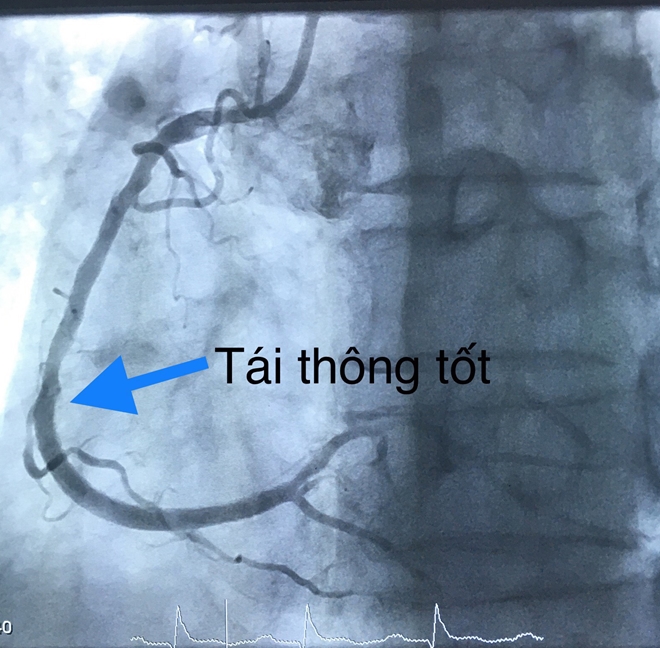

Tại đây, bệnh nhân được chẩn đoán nhồi máu cơ tim cấp thành dưới giờ thứ 4 biến chứng ngưng tim do rối loạn nhịp (rung thất) đã cấp cứu thành công. Bệnh nhân được chỉ định chụp, can thiệp mạch vành cấp cứu và chuyển thẳng đến phòng can thiệp.

Các bác sĩ tiến hành dùng bóng nong động mạch vành phải và đặt một stent phủ thuốc. Thời gian tái thông mạch vành 20 phút.

Hình ảnh tắc động mạch vành.